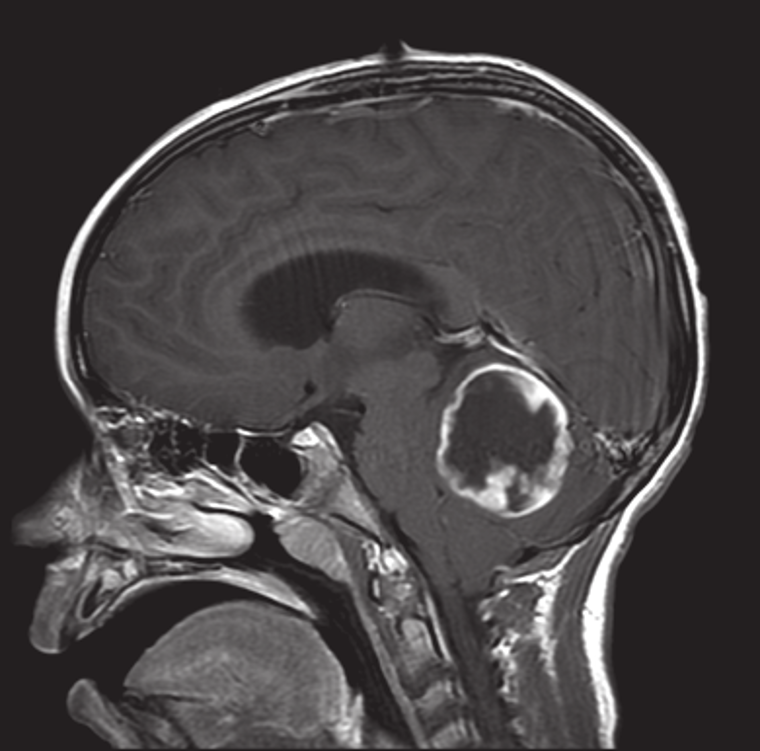

You see a patient with this MRI. What histologic findings would you expect if this was found to be a glial neoplasm?

This MRI demonstrates evidence of what process? A. Metastases B. Alcoholic cerebellar degeneration C. Turcot’s syndrome D. Lhermitte-Duclos disease

A. Metastases B. Alcoholic cerebellar degeneration C. Turcot’s syndrome **D. Lhermitte-Duclos disease** ## Footnote This MRI demonstrates findings consistent with Lhermitte-Duclos disease, with evidence of hypertrophic cerebellar folia. Further Reading: Psaaros. The Definitive Neurosurgical Board Review, page 129.

What gene mutation is often linked with patients exhibiting the findings as shown under Question 29? A. P53 B. SHH C. PTEN D. H-ras

A. P53 B. SHH **C. PTEN** D. H-ras ## Footnote This MRI demonstrates findings consistent with Lhermitte-Duclos disease, with evidence of hypertrophic cerebellar folia. This finding can be seen in patients with Cowden’s syndrome, often caused by a mutation in PTEN. Further Reading: Psaaros. The Definitive Neurosurgical Board Review, page 129.